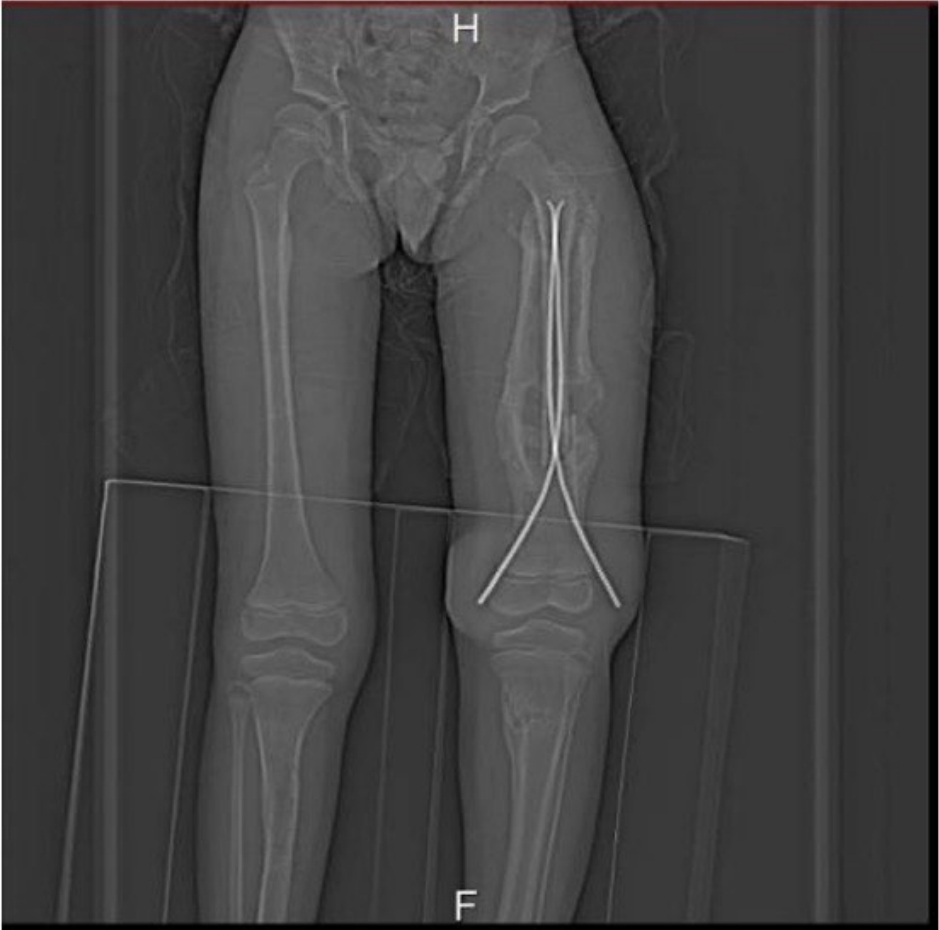

After 5 months, the patient sustained a left femur fracture and was initially stabilized with a temporary back slab, later undergoing surgical intervention with elastic nailing. Persistent concerns regarding abnormal bone healing and possible infection prompted advanced imaging 3 months postoperatively. A Tc99m bone scan revealed active lesions in the femur and tibia (

Fig. 1). Computed tomography confirmed chronic osteomyelitis (

Fig. 1.Tc99m MDP bone scan (triple-phase bone scan). Written informed consent for the publication of this image was obtained from the patient.